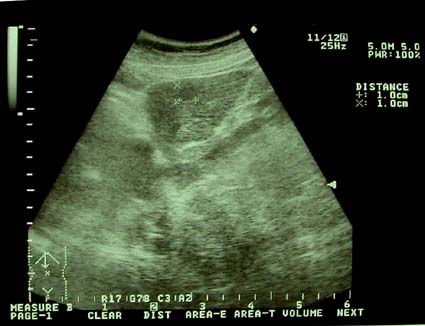

3:腹部超音波検査 予約なしで

いつでも検査可能です

腹部全域における内臓臓器の異常を調べます。ゼリーをつけたプローブを体に当てるだけですから全く侵襲のない検査といえます。具体的には肝臓、胆嚢、膵臓、脾臓、腎臓、膀胱、前立腺、子宮、卵巣などを調べたり、胸水や腹水の貯留について調べることができます。超音波は、ガスがあると画像が不鮮明になるので消化管の描出は困難ですが、大きい腫瘍や強い炎症があると消化管でも描出が可能な場合があります。

レントゲンと違いX線の被爆もありません。